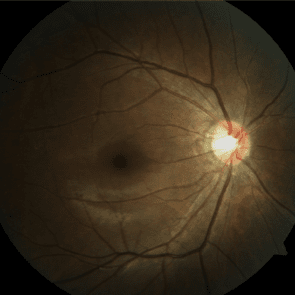

정상시신경 유두

손상되어 커진 시신경 유두